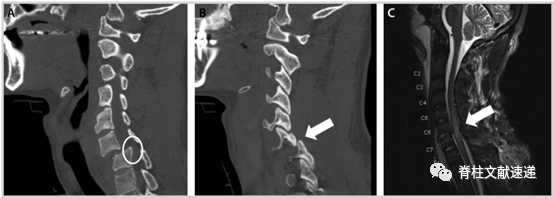

MRI能够准确的判断脊柱、脊髓损伤程度,特别是当CT提示脊髓、椎间盘等可能存在损伤或无法解释的神经系统检查时,MRI可以帮助我们早期诊断、估计预后(椎管内出血(> 1cm长)以及T2信号纵向改变> 3cm与预后不良有关,正常的MRI结果通常预示患者能够恢复正常)及制定治疗决策。

图注:图A、B为C6-7脱位的CT结果,图C为MRI的T2加权像结果显示以C6-C7为中心的外伤性脊髓损伤, C5至T1均存在不同程度的脊髓信号异常。